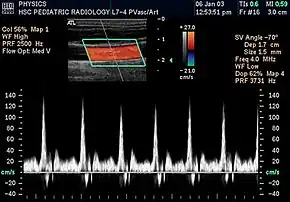

Doppler ultrasonography is widely used in renal ultrasonography. Renal vessels are easily depicted by the color Doppler technique in order to evaluate perfusion. Applying spectral Doppler to the renal artery and selected interlobular arteries, peak systolic velocities, resistive index, and acceleration curves can be estimated (Figure 4) (e.g., peak systolic velocity of the renal artery above 180 cm/s is a predictor of renal artery stenosis of more than 60%, and a resistive index, which is a calculated from peak systolic and end systolic velocity, above 0.70 is indicative of abnormal renovascular resistance).[12]